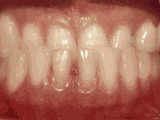

Apiñamiento de dientes

El paciente inició su tratamiento a la edad de 11 años y usó frenos por 26 meses. Está muy feliz con su nueva sonrisa.